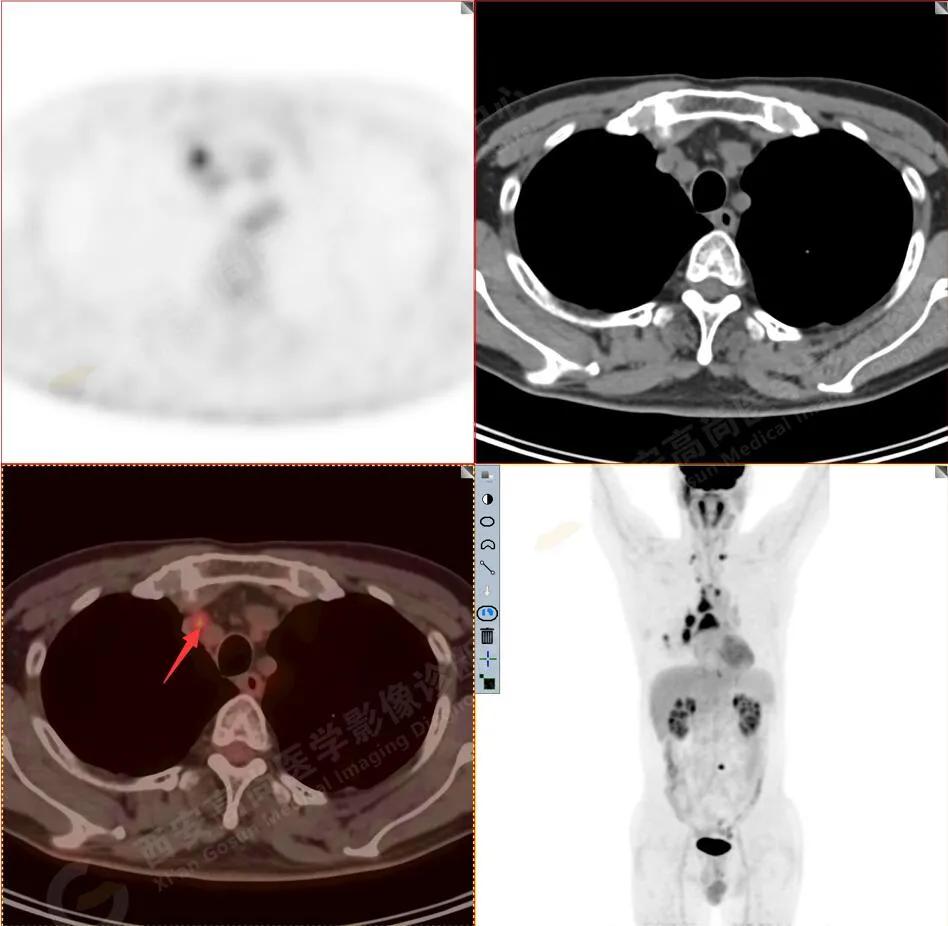

2R组淋巴结转移

3.右侧肺门、纵隔(1L、1R、3A、4、6、7组)及双侧锁骨上多发肿大淋巴结,呈不同程度FDG代谢异常增高,考虑为淋巴结转移。